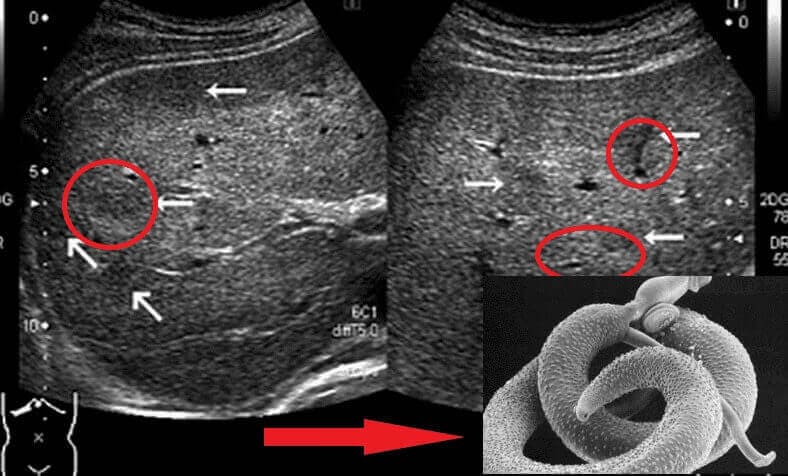

Beberapa kes jangkitan parasit dan risikonya

— Baru semalam, saya terlibat dalam pemeriksaan wanita berusia 51 tahun yang dimasukkan ke ICU akibat pembedahan serangan jantung. Hasil kajian menunjukkan saluran arteri beliau menyempit teruk. Yang lebih mengejutkan, imej X-ray menunjukkan sesuatu yang aneh. Setelah pemeriksaan lebih lanjut, didapati ada kista yang mengandungi parasit di dalam paru-paru!

Seorang lelaki berusia 61 tahun pula menjalani pemeriksaan kerana kerosakan hati yang serius. Keluarga sangka puncanya minum alkohol. Namun ujian mendapati hati beliau “digerudi” puluhan parasit sehingga membentuk banyak lorong di dalam tisu.

Dan satu lagi kes agak mengejutkan. Pemeriksaan otak pesakit berusia 49 tahun menemui parasit bersama larva mereka berselerakan di seluruh tisu otak. Awalnya, disyaki strok iskemia, tapi punca sebenar rupanya jangkitan parasit yang merosakkan otak.

Parasit memakan sel otak sementara pesakit masih hidup! Pesakit cuma rasa sakit kepala kronik.

Beliau mengalami migrain berpanjangan, insomnia beberapa tahun, dan serangan sawan apabila parasit mulai memakan bahagian otak. Bila disiasat, punca sebenarnya adalah kemusnahan tisu otak akibat parasit.

“Pergerakan” parasit yang dirakam dalam usus.